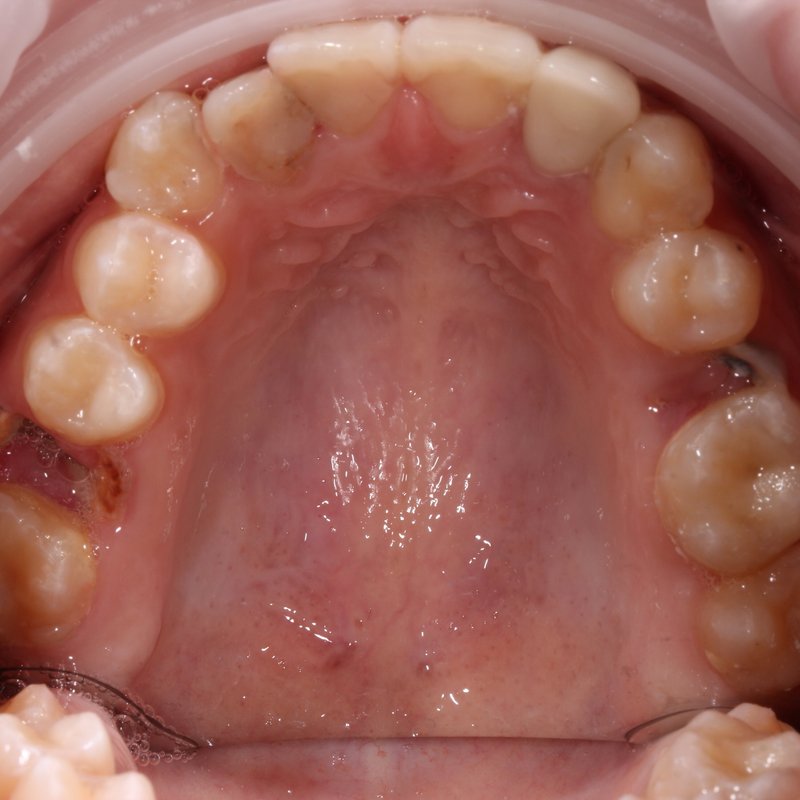

Фотогалерея